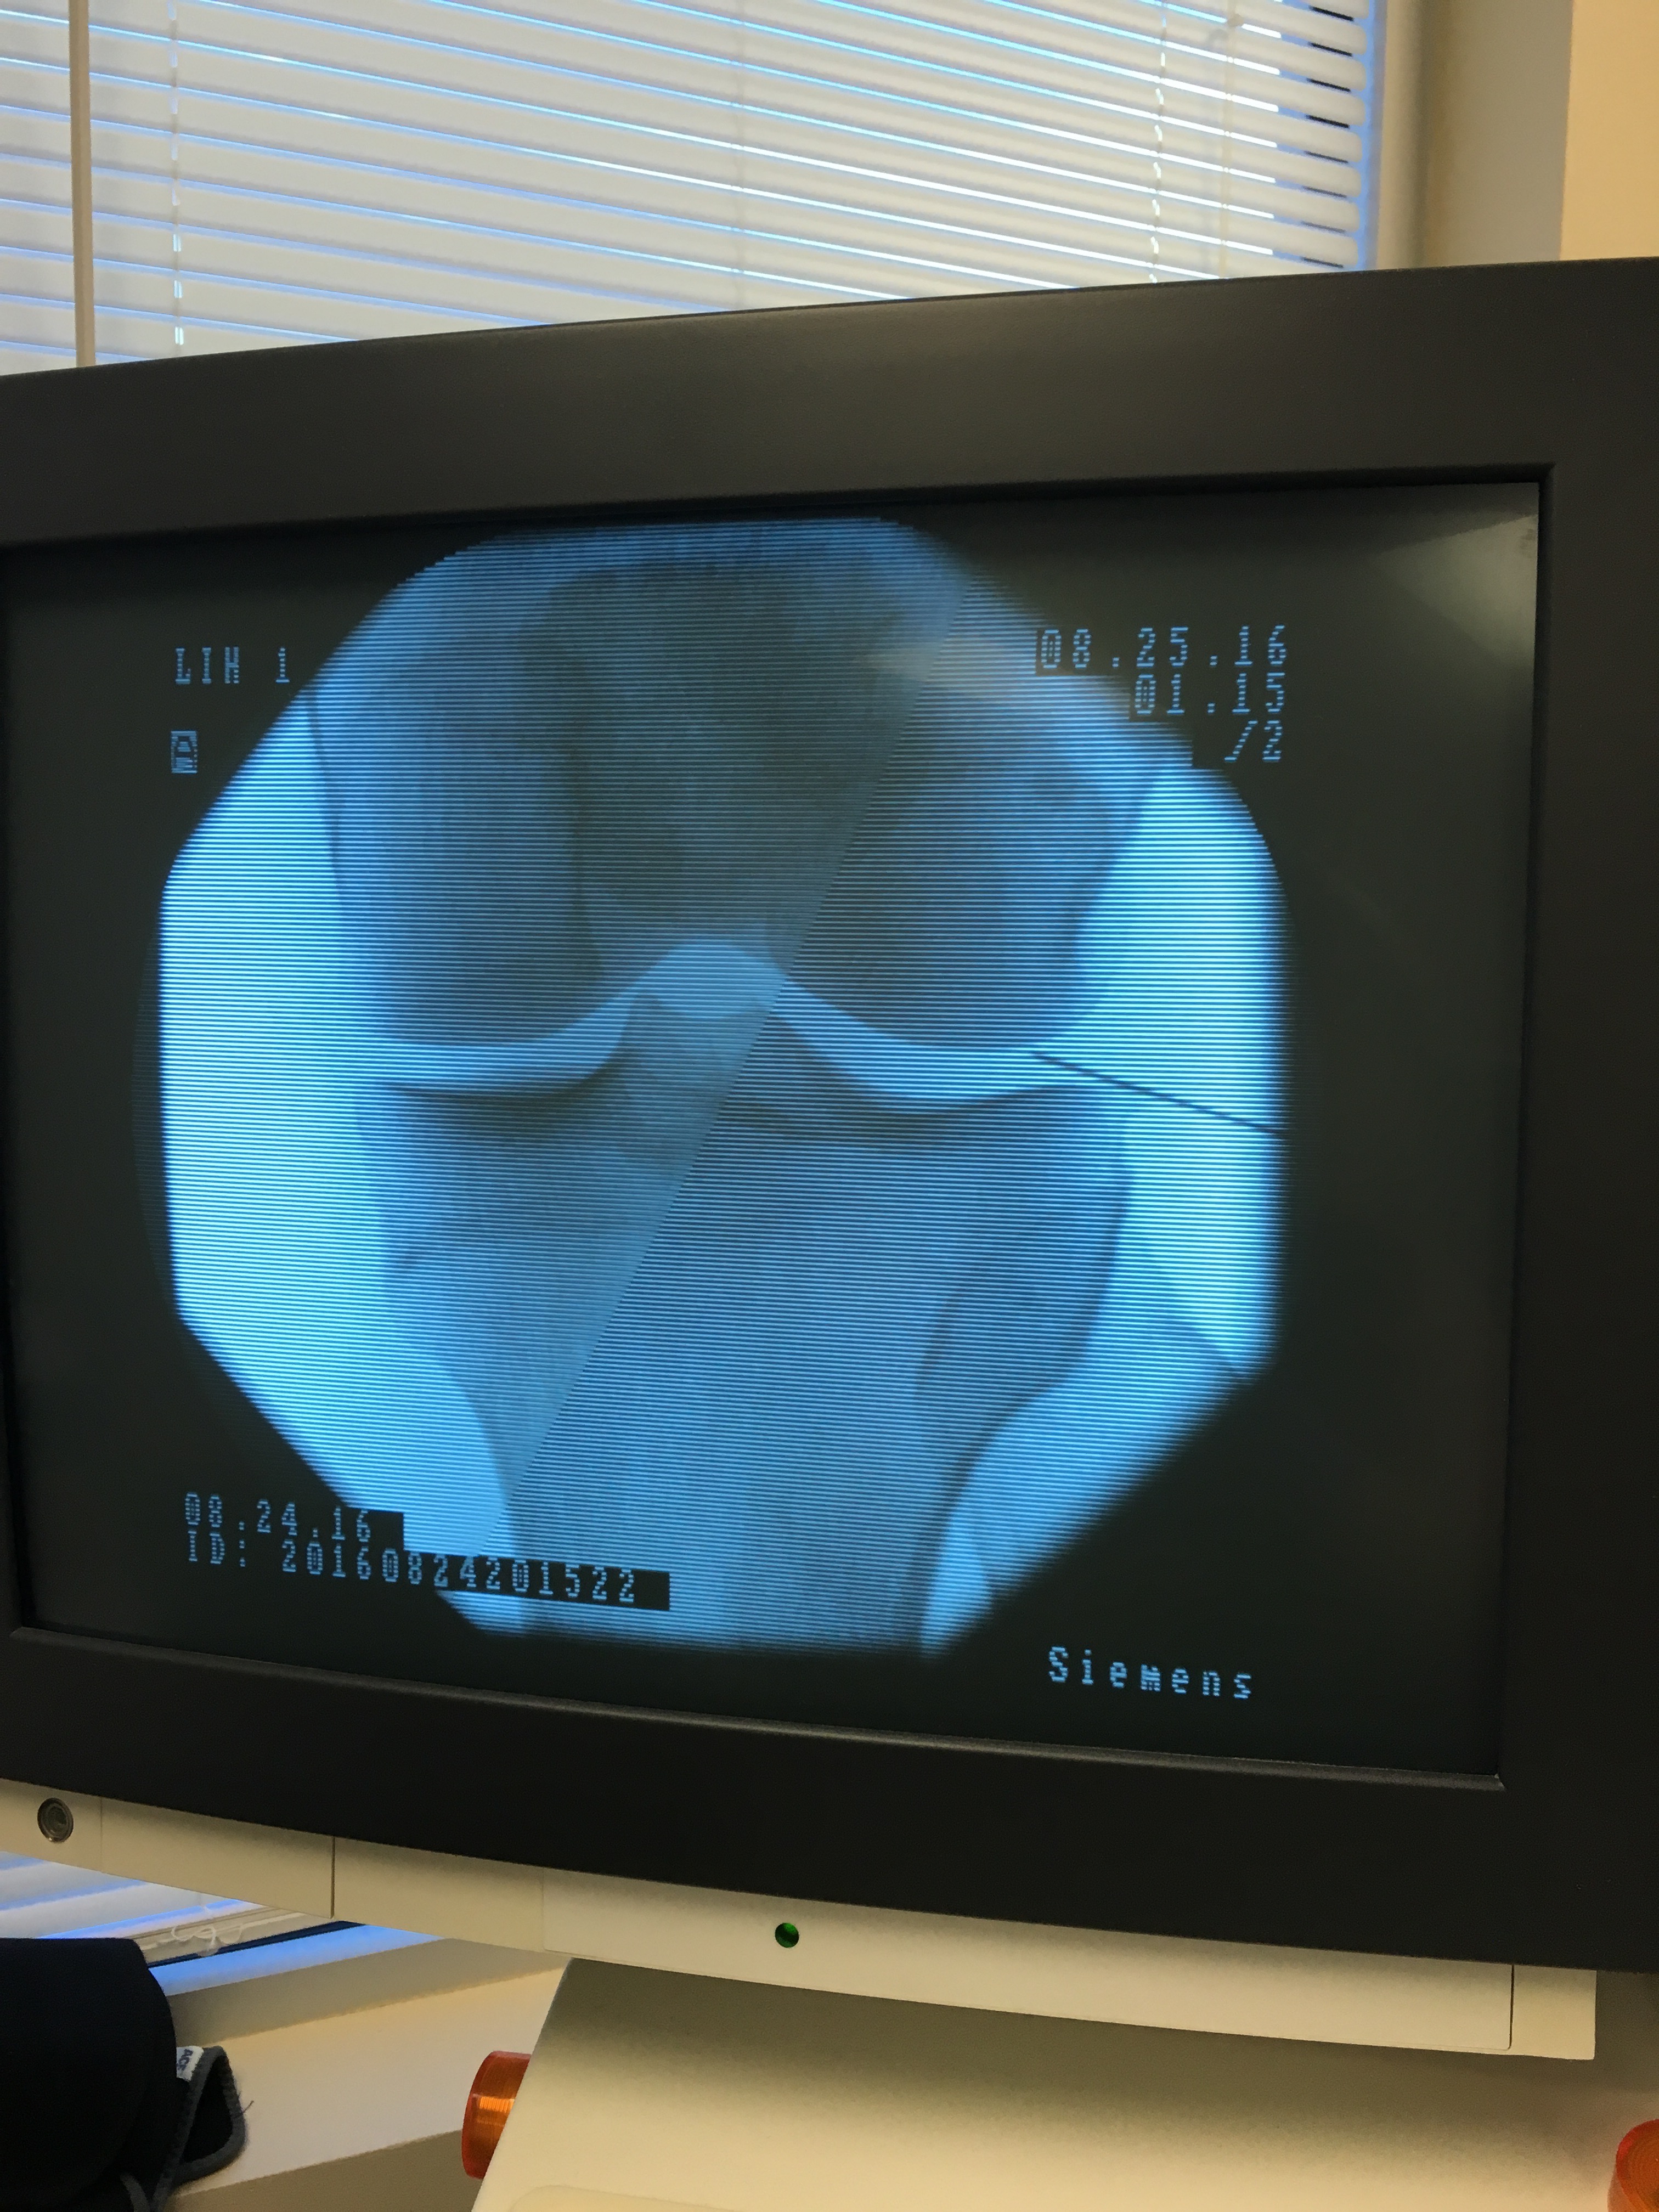

IMG_5491

One of my knees and needle inserted.

My Stem Cell Procedure